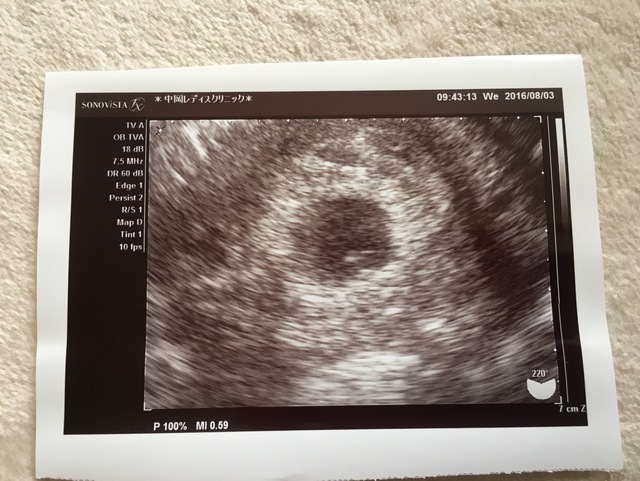

みなさんにお寄せいただいた妊娠5週目のエコー写真とエピソードをご紹介しました。